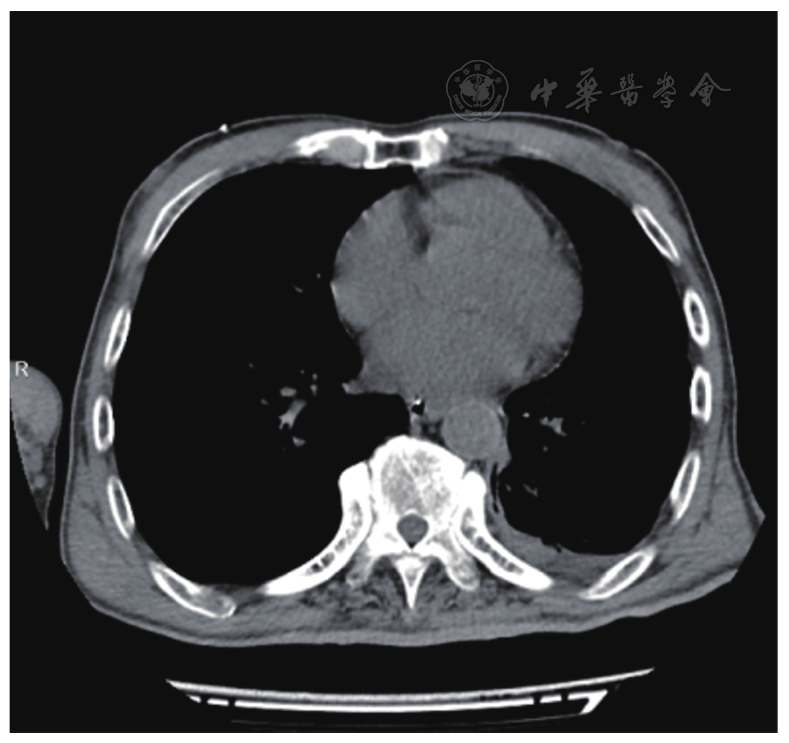

图1 入院时CT提示纵隔气肿,左侧少许积液。CT:计算机断层扫描